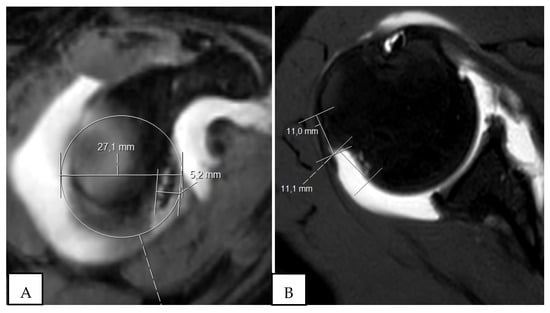

2. The Glenoid Track and Hill–Sachs Lesions: On-Track and Off-Track